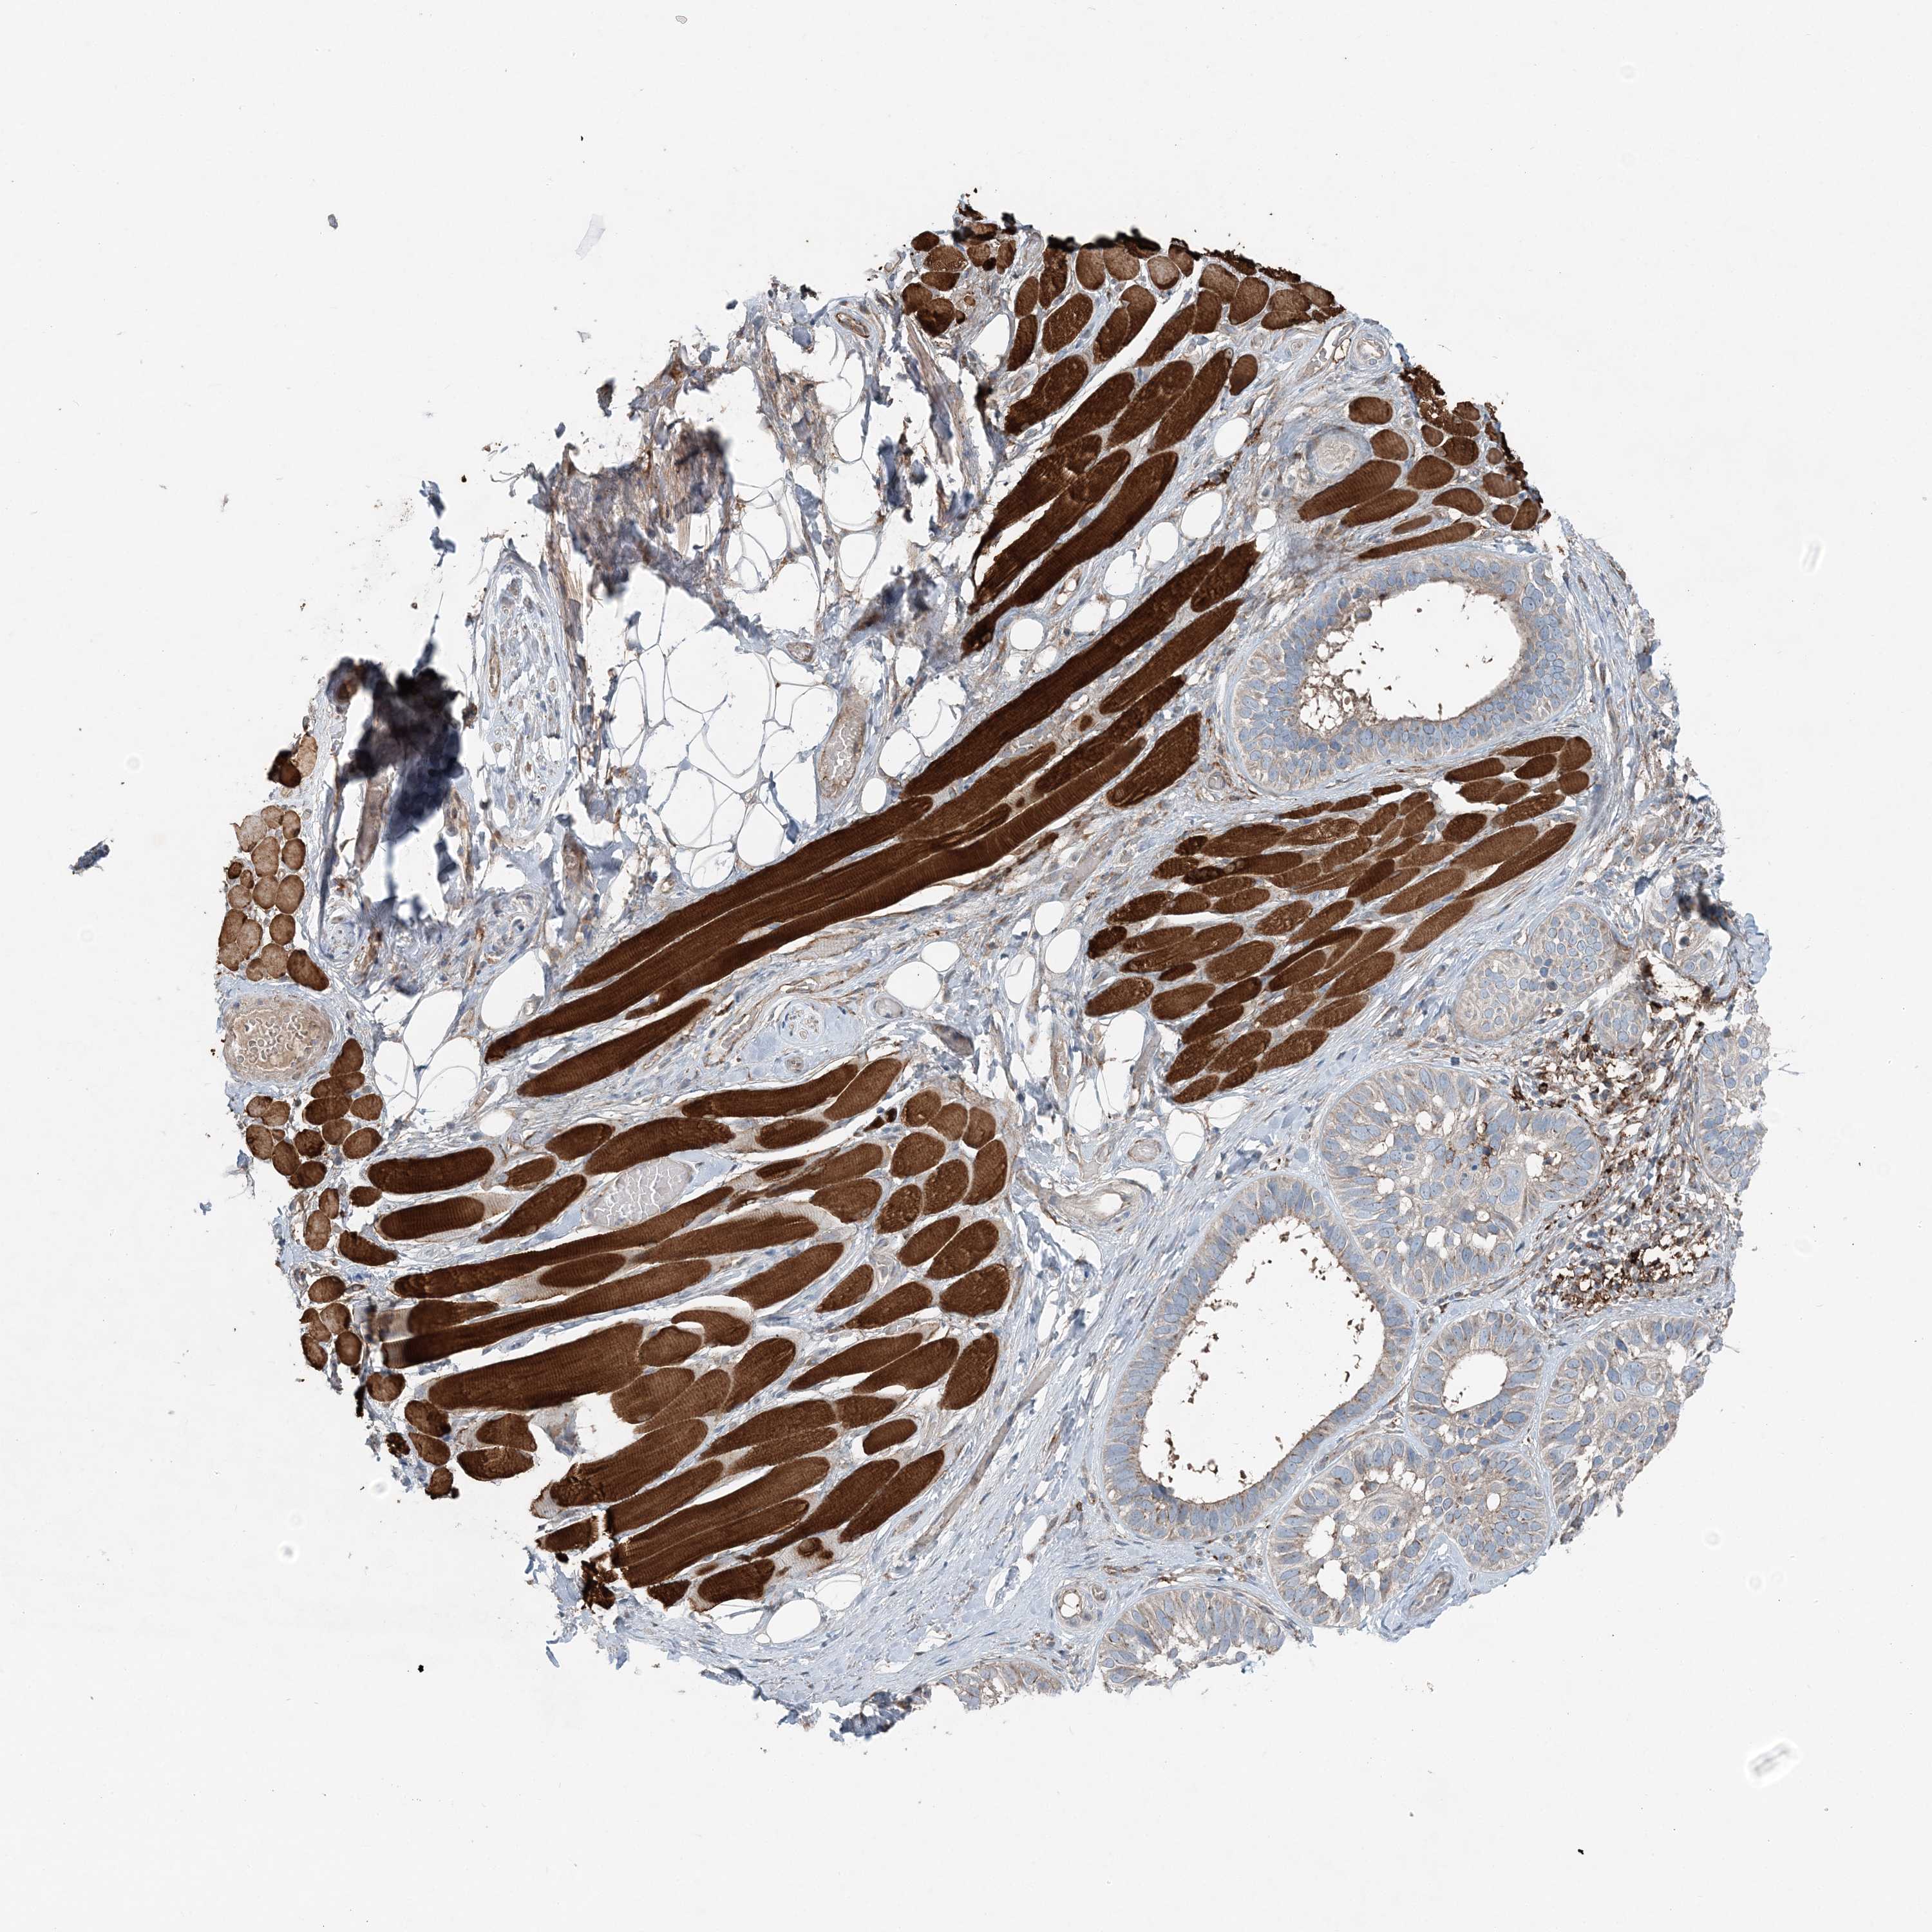

SKIN CANCER - Protein expressioni

A mouse-over function shows sample information and annotation data. Click on an image to view it in a full screen mode. Samples can be filtered based on level of antibody staining by selecting one or several of the following categories: high, medium, low and not detected. The assay and annotation is described here.

Antibody stainingi

Antibody staining in the annotated cell types in the current human tissue is reported as not detected, low, medium, or high, based on conventional immunohistochemistry profiling in selected tissues. This score is based on the combination of the staining intensity and fraction of stained cells.

Each image is clickable and will lead to virtual microscopy that enables deeper exploration of all samples and also displays staining intensity scores, fraction scores and subcellular localization as well as patient and tissue information for each sample.

Antibody HPA036668

Squamous cell carcinoma, NOS